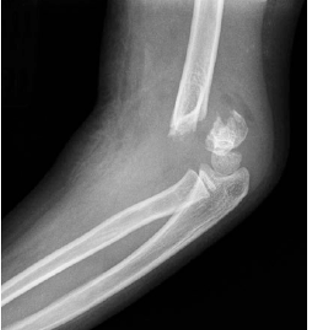

Hình 4: Gãy trên lồi cầu xương cánh tay độ III với sự di lệch hoàn toàn đầu gãy xa ( (Courtesy of Joshua M. Abzug, MD)